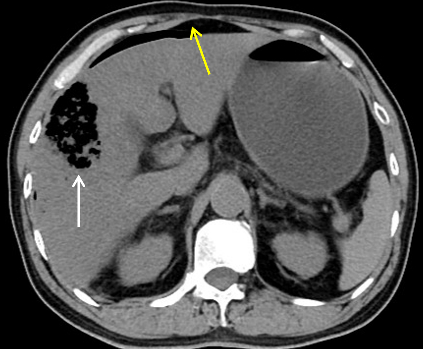

今晨零点左右上厕所后再发畏寒发热,家属发现其口唇发紫、呼吸急促,遂来本院急诊。腹部CT平扫提示肝内积气(图 2)。收住急诊抢救室,急查腹部增强CT,考虑肝脓肿致肝脏破裂(图 3)。

| 图 2 患者全腹部CT平扫示肝V段见团片状气体密度影(白色箭头所指处),腹腔可见大量游离气体(黄色箭头所指处) |

图 2患者全腹部CT平扫示肝V段见团片状气体密度影(白色箭头所指处),腹腔可见大量游离气体(黄色箭头所指处)。